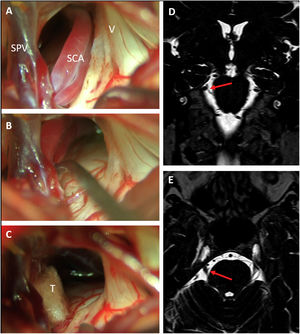

Surgical techniqueThe operations were performed under general anesthesia with the patient in a three-quarter prone position. A standard lateral suboccipital retrosigmoid craniectomy exposing the limits of the transverse and sigmoid sinus was employed to gain access to the CPA. Microsurgical inspection of the CPA with careful dissection of arachnoid attachments allowed for ample exposure of the subarachnoid course of the trigeminal root and its vascular relations. Afferents to the superior petrous vein complex were spared whenever possible, although in cases where exposure of the nerve was severely limited by veins, some afferents were selectively coagulated and sectioned. MCV was performed following the principles described by Jannetta.21,22 In cases of arterial compression, a vessel transposition away from the nerve was attempted and one or more Teflon pledgets were interposed between the artery and the nerve. In cases of venous compression, Teflon decompression, or venous coagulation and sectioning were chosen depending on the caliber of the vein and its disposition. In cases that did not exhibit any vascular compression after thorough exploration, a partial sensory rhizotomy (PSR) was performed (Fig. 1). PSR is an ablative procedure that intentionally damages the nerve providing effective and lasting pain relief in a rate at least comparable to other ablative procedures such as percutaneous trigeminal gangliolysis.23 It may be an acceptable option when no vascular compression can be proven. Since there is no evidence that PSR enhances the results of MVD and because of its ablative nature, it always implies some degree on sensory deficit which in rare cases may cause anesthesia dolorosa,23 we only consider PSR for cases without neurovascular compression or for repeat operations after failed MVD.

Right trigeminal neuralgia caused by a descending loop of the superior cerebellar artery (SCA) as seen on preoperative coronal (D) and axial (E) DRIVE-MRI sequences. Microsurgical inspection revealed a double arterial loop corresponding to the superior and inferior branches of the SCA compressing the superomedial portion of the trigeminal nerve (A). After dissection of the arachnoid adhesions, the arteries could be transposed cranially (B) and held in place with a Teflon pledget (C). SPV: Superior petrosal vein; SCA: Superior cerebellar artery; V: Fifth cranial nerve; T: Teflon pledget.